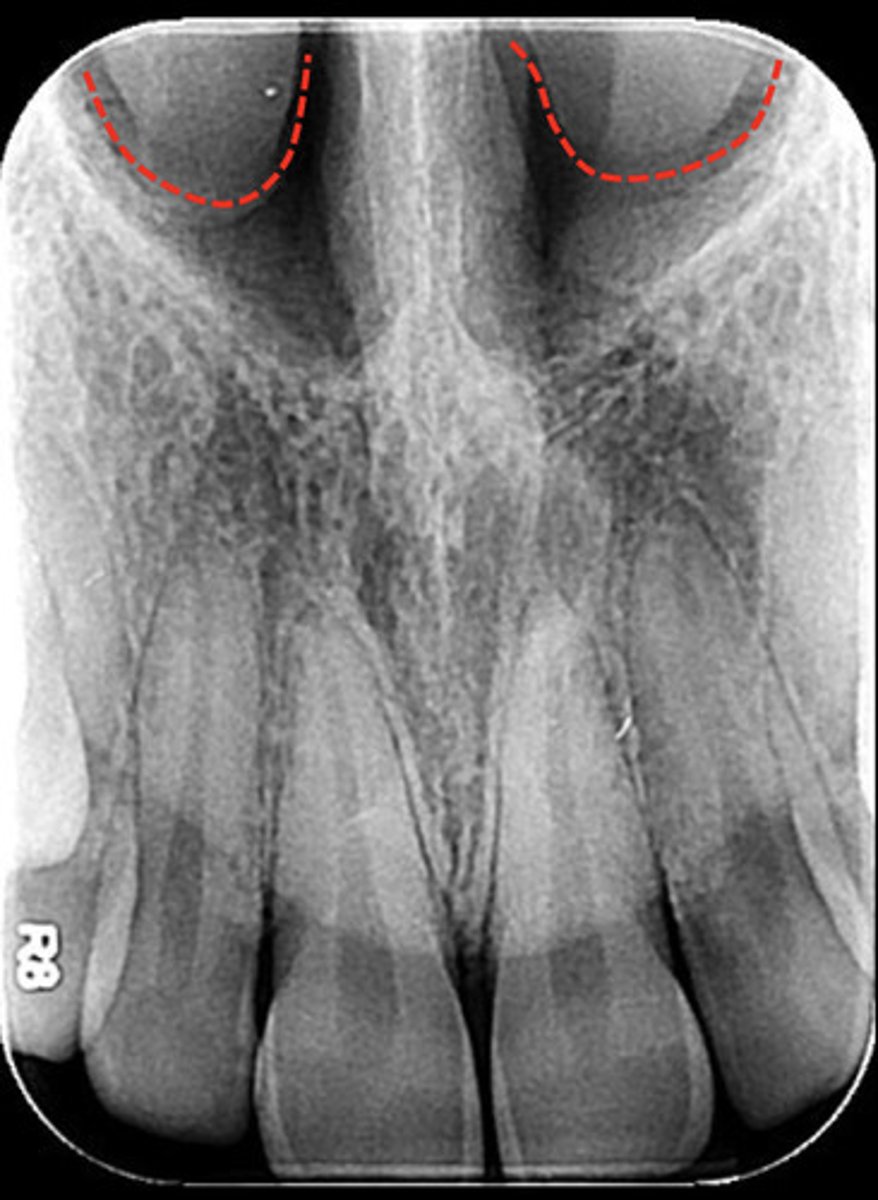

What are the red dotted lines representing?

Nasal cavity - nasal fossae

What are the red dotted lines circling?

inferior nasal conchae